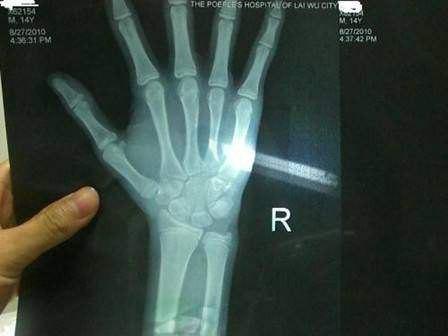

例如男孩12周岁,骨龄在11-13周岁区间是正常,骨龄大于或小于实际周岁2年以上,就要警惕内分泌疾病或早发育。

特别注意:一般孩子在14、15岁时骨骺就接近闭合,生长基本停止。家长不能盲目等待孩子“晚长”,最终会耽误孩子成年身高。